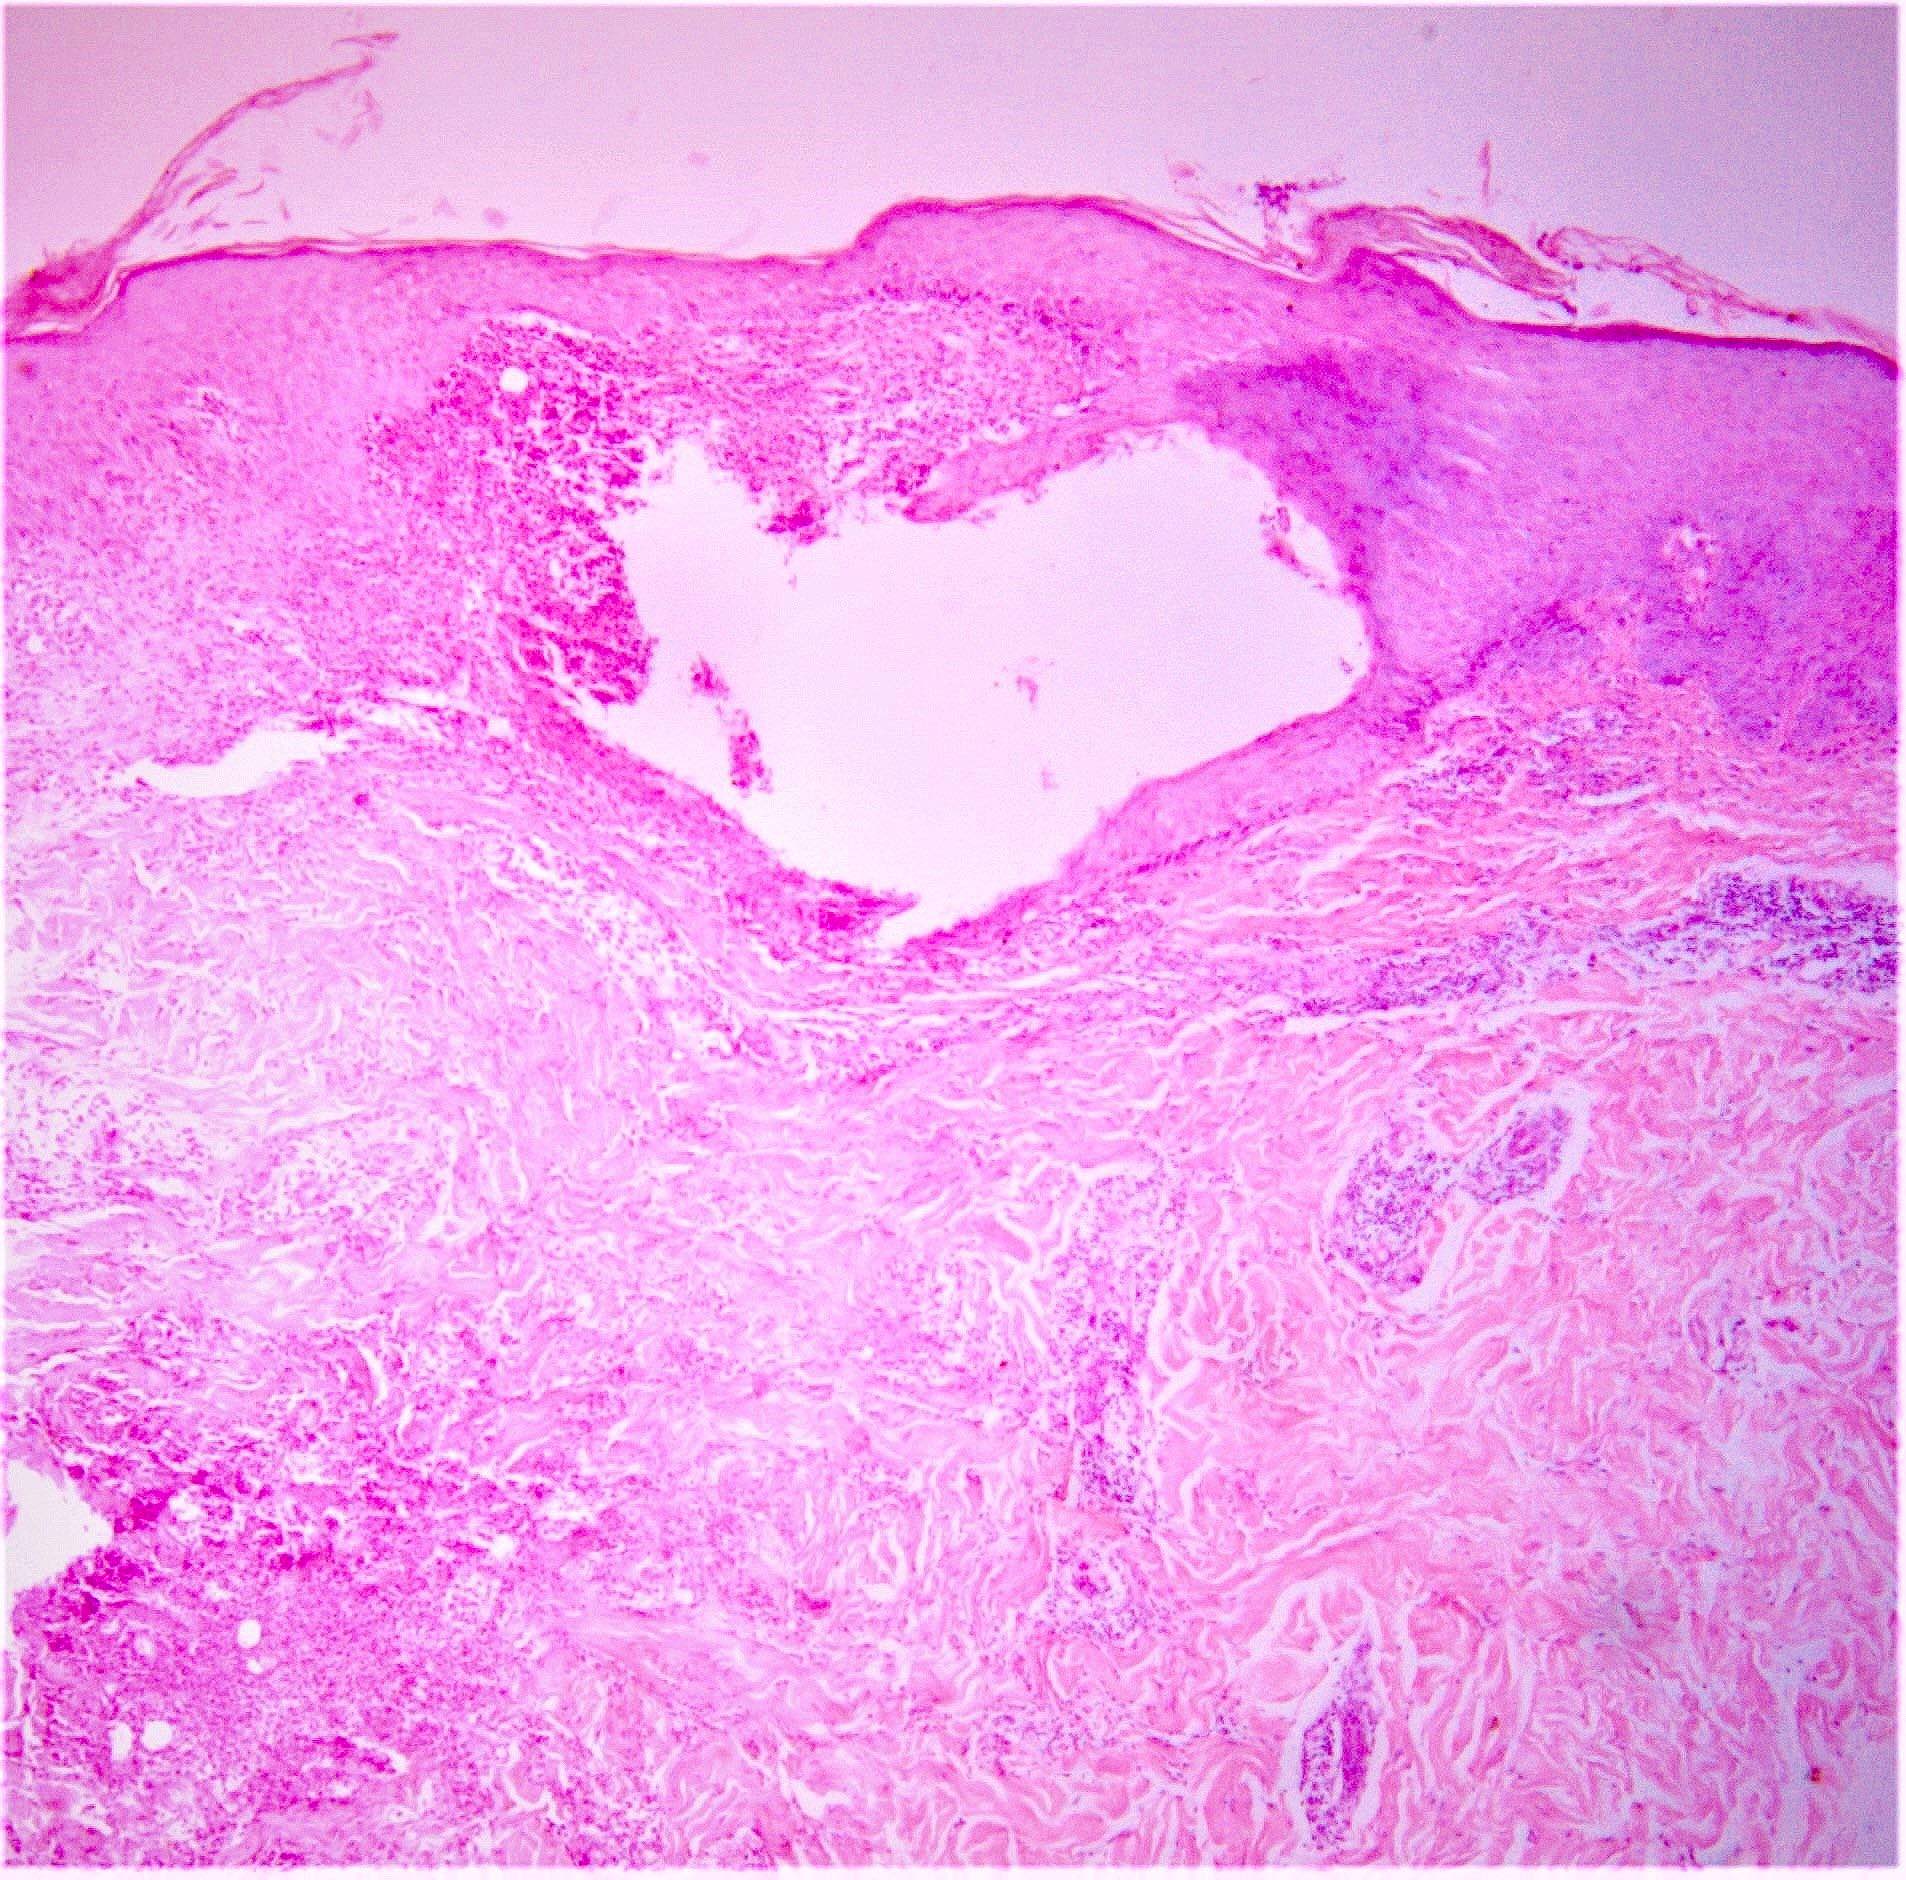

Microscopic (histologic) description

- Oral and genital ulcers: not specific; mixed dermal inflammatory infiltrate perivascular and at the base of the ulcer

- Erythema nodosum-like lesions: septal panniculitis; vasculitis (lymphocytic or neutrophilic) and necrobiosis may be found

- Pathergy reaction: perivascular infiltrate of mononuclear cells; mast cell infiltrate and neutrophilic vasculitis may be found

- Papulopustular lesions: spongiosis, basal keratinocyte vacuolization, intraepidermal pustules, suppurative folliculitis

- Thrombophlebitis: thrombi in vessel lumens, perivascular inflammatory infiltrate

- Leukocytoclastic vasculitis

- Reference: Patholog Res Int 2012;2012:209316

Microscopic (histologic) images